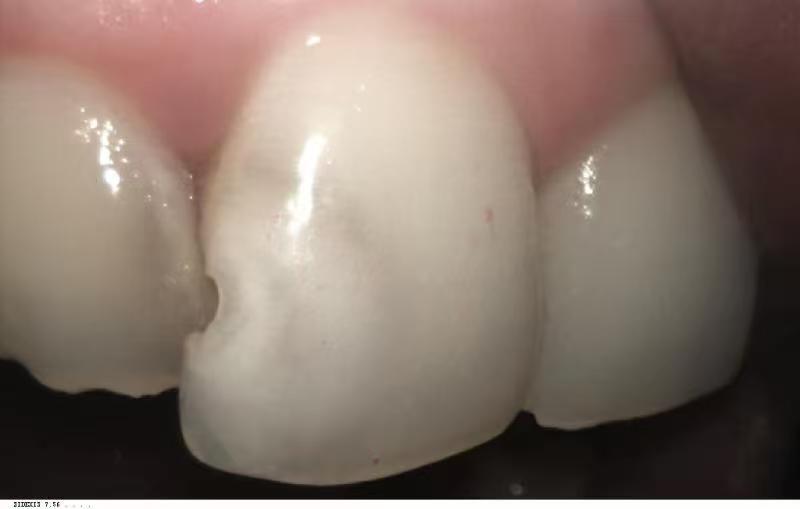

Oral health plays a vital role in daily life. Healthy teeth allow individuals to eat, speak, and smile confidently. However, neglecting dental care can lead to severe consequences. For example, tooth decay is a common problem that affects many people. It can occur even with good hygiene practices due to factors like genetics and diet. In fact, many people experience dental issues despite their best efforts. A personal story illustrates this point: a front tooth began to decay, gradually worsening over the years. Although the initial damage seemed minor, it eventually required extensive treatment. This emphasizes the importance of addressing dental problems early to prevent further complications.

Through the consultation, a root canal procedure was recommended. Surprisingly, the cost was reasonable compared to other options. Temporary fillings provided relief while waiting for a more permanent solution. After nearly a year (not recommended though this was not per doctor’s instruction. ), a follow-up appointment resulted in a thorough filling that restored the tooth’s function and appearance. The dedication of the dental professionals made a significant impact on the overall experience, illustrating the value of choosing the right dental care provider.